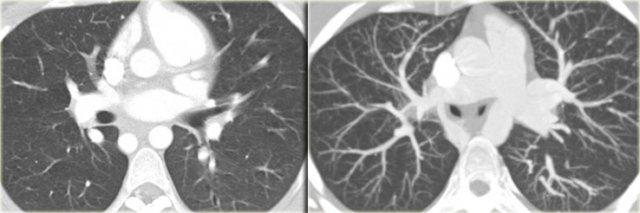

Right Arch Mirror Image

This is the mirror-image variety of the left arch.

On the left a 2 year old girl with wheezing and coughing.

On the axial image there is a right arch

On the volume rendered image there is mirror image branching of the brachiocephalic arteries, no aberrant subclavian artery, so this is a right arch mirror image.

This anomaly is asymptomatic, because there is no obstructing ring.

Almost all of these patients however come to our attention because they have associated congenital heart disease in 98% of cases.

This patient had a mirror image aortic arch and a VSD.

On the left an adult who was operated in his childhood for a Tetralogy of Fallot (pulmonary stenosis, right ventricular hypertrophy, VSD, overriding aorta).

At surgery the VSD was patched and the pulmonary outflow tract was enlarged.

Notice that there is also a right arch.